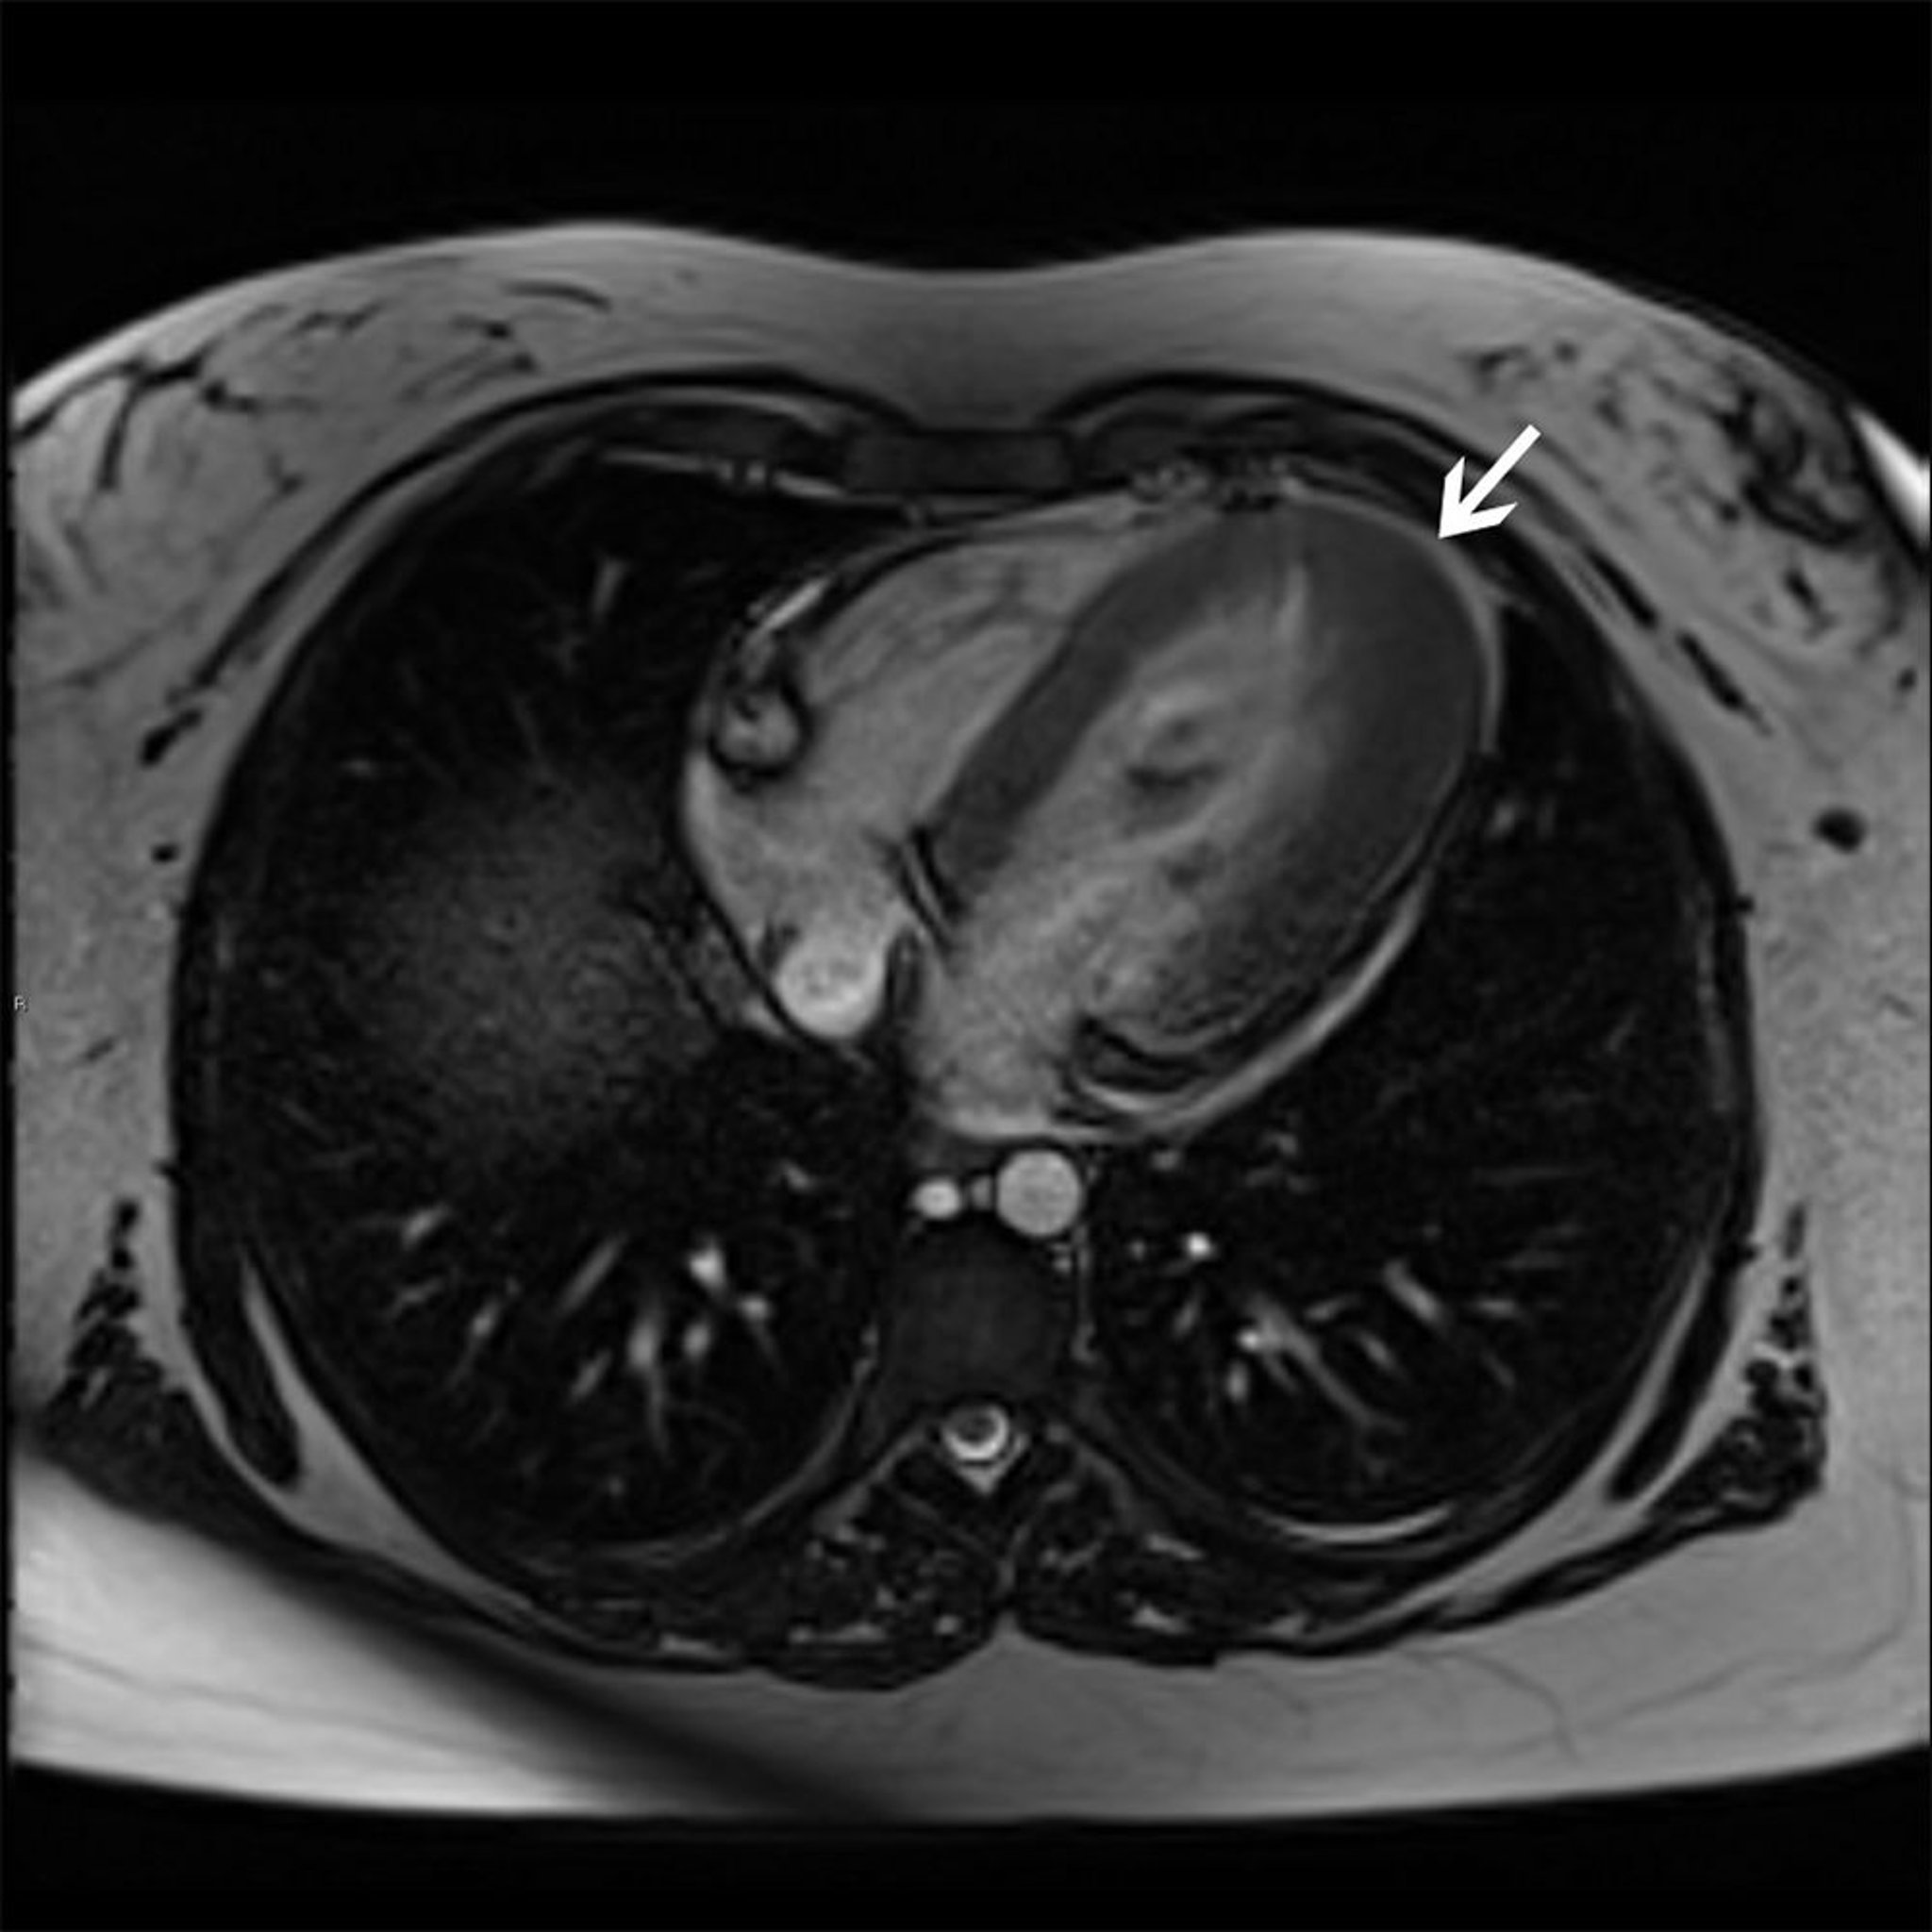

Miocardiopatía hipertrófica (variante apical)

Esta resonancia magnética cardíaca muestra una variante de hipertrofia apical (flecha) de miocardiopatía hipertrófica.